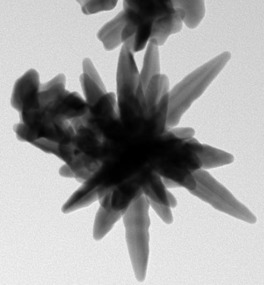

Ученые из Национального технологического университета «МИСиС» (Москва, Россия) совместно с коллегами из Института ядерной физики имени Саха (Калькутта, Индия) смогли синтезировать стабильные золотые наночастицы в форме звезд для борьбы с онкологическими заболеваниями. Недорогие и нетоксичные наночастицы позволят эффективно диагностировать рак на ранних стадиях и точечно уничтожать пораженные клетки. Результаты исследования опубликованы в научном издании Journal of the Chemical Society.

Сегодня в медицине активно используются плазмонные наноматериалы на основе серебра и золота. «Плазмонными» называют наноструктуры, необычные оптические и физические свойства которых обусловливаются прежде всего их формой и структурой, а также колебанием свободных электронов внутри них. То, каким образом происходит это колебание, сильно зависит от формы и размера наночастиц. Именно это позволяет им иметь набор необычных оптических и физических свойств.

4500-5000 600-900 нанометров. пояснил руководитель инфраструктурного проекта НИТУ «МИСиС» «Получение, характеризация и применение функционализированных анизотропных наноматериалов в селективном обнаружении биомаркеров, ультраточном количественном анализе и терапии» профессор Института ядерной физики имени Саха Дулал Сенапати.